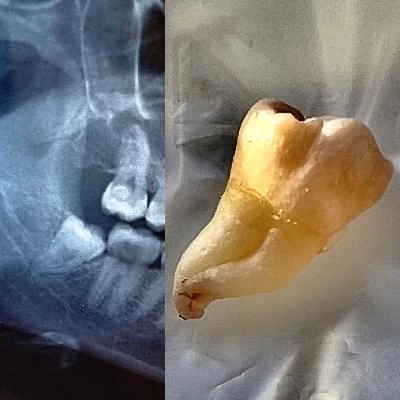

الدكتور فتح اله عباسپور طبيب أسنان

مجال النشاط الدكتور فتح اله عباسپور طبيب أسنان

• جراحی دندان عقل نهفته بسیار عالی بودند و تشخیص ایشون عالی بود